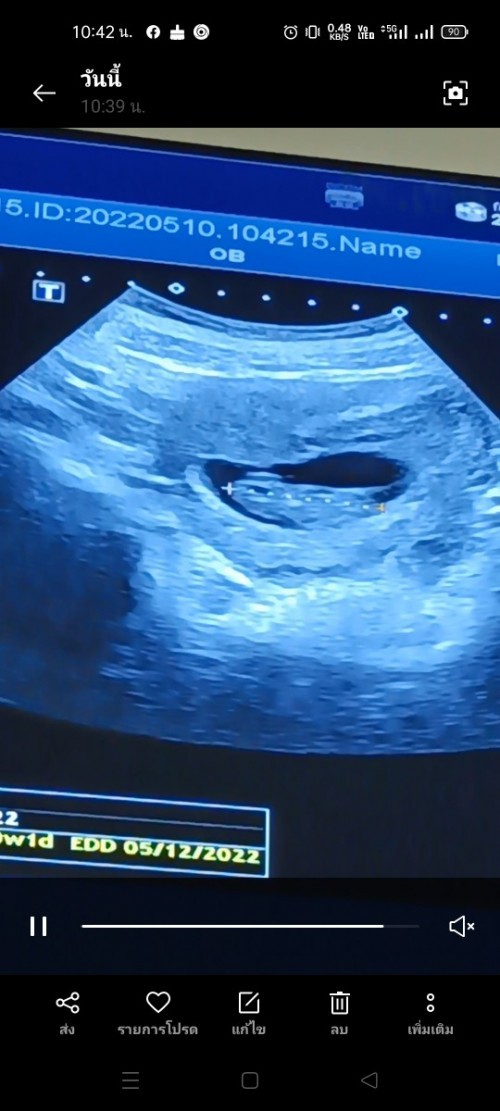

10week เหมือนก้อนอะไรไม่รู้

Post reply image